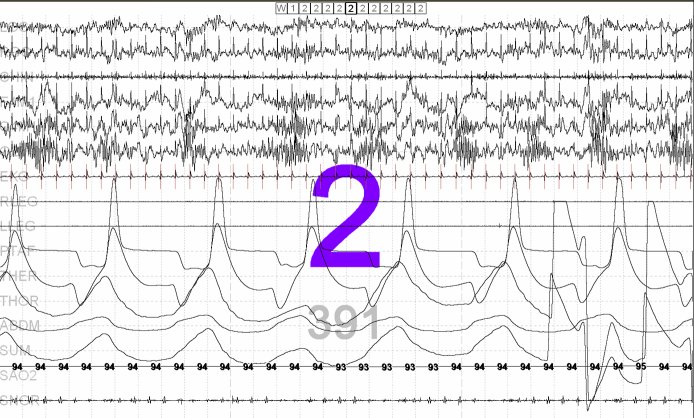

- This record demonstrates an epoch of N2 sleep, with very frequent spindles seen in the EEG leads (see answer fragment below). This is a frequent finding with benzodiazepine medications. Sleep spindles can also be seen with barbiturates and alcohol.